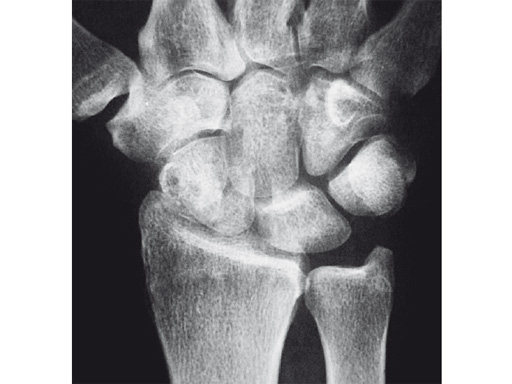

Fig 1 X-ray shows SNAC wrist.